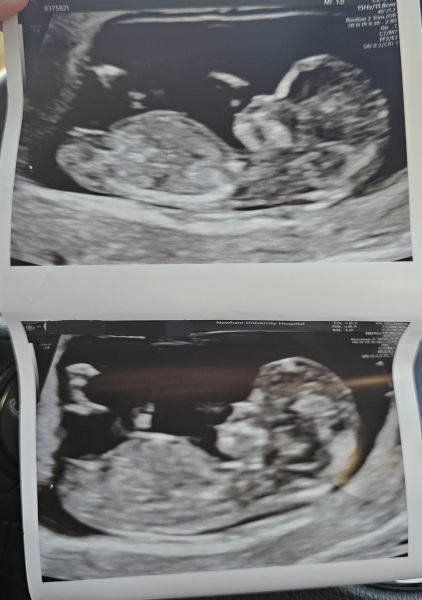

Boy or girl by nub and skull theory?!

Just had my dating scan which is showing I am 12 weeks 1 day. I was wondering if any nub experts here can tell if it's a boy/girl?! Just abit of fun !

I’d say girl

I also think girl, based on nub and skull. Congratulations!

I'm going girl.

Google skull theory boy vs girl and looks at the forehead and nose area

Google nub theory and looks at the nub . If it point up it's a hit if it doesn't it a girl ... in theory

Although it does look pretty parallel with the spine now, as this scan was closer to the 12 week mark I'm just thinking that the nub still has time to rise haha